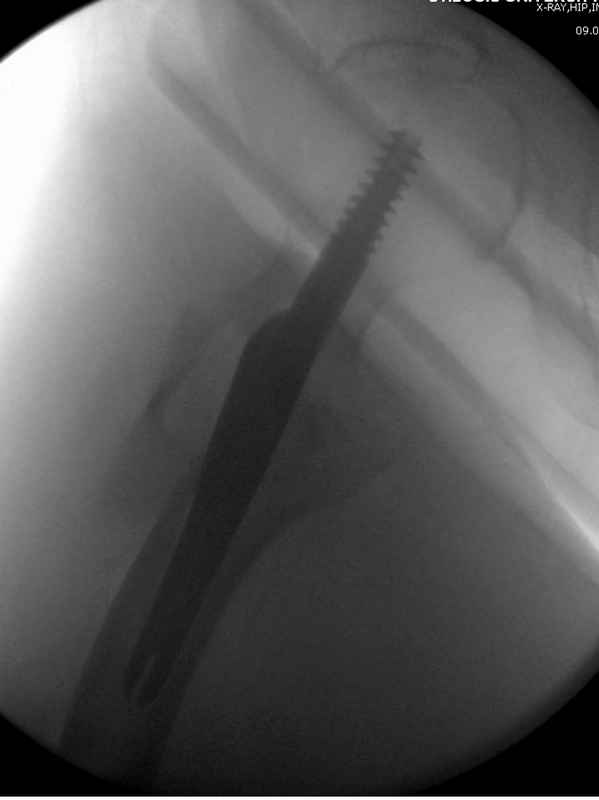

Здесь 83 года, травма в результате падения

Djoldas Kuldjanov, M.D.

Department of Orthopedic Surgery

St. Louis University